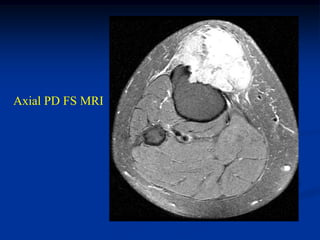

Case # 124.1                    AP and lat x-ray

50 year male with chondromyxoid fibroma proximal

tibia with 6 months of a tender tumor mass anterior tibia

Coronal T-1 MRI

Coronal PD FS MRI

Axial PD FS MRI

Axial Gad MRI